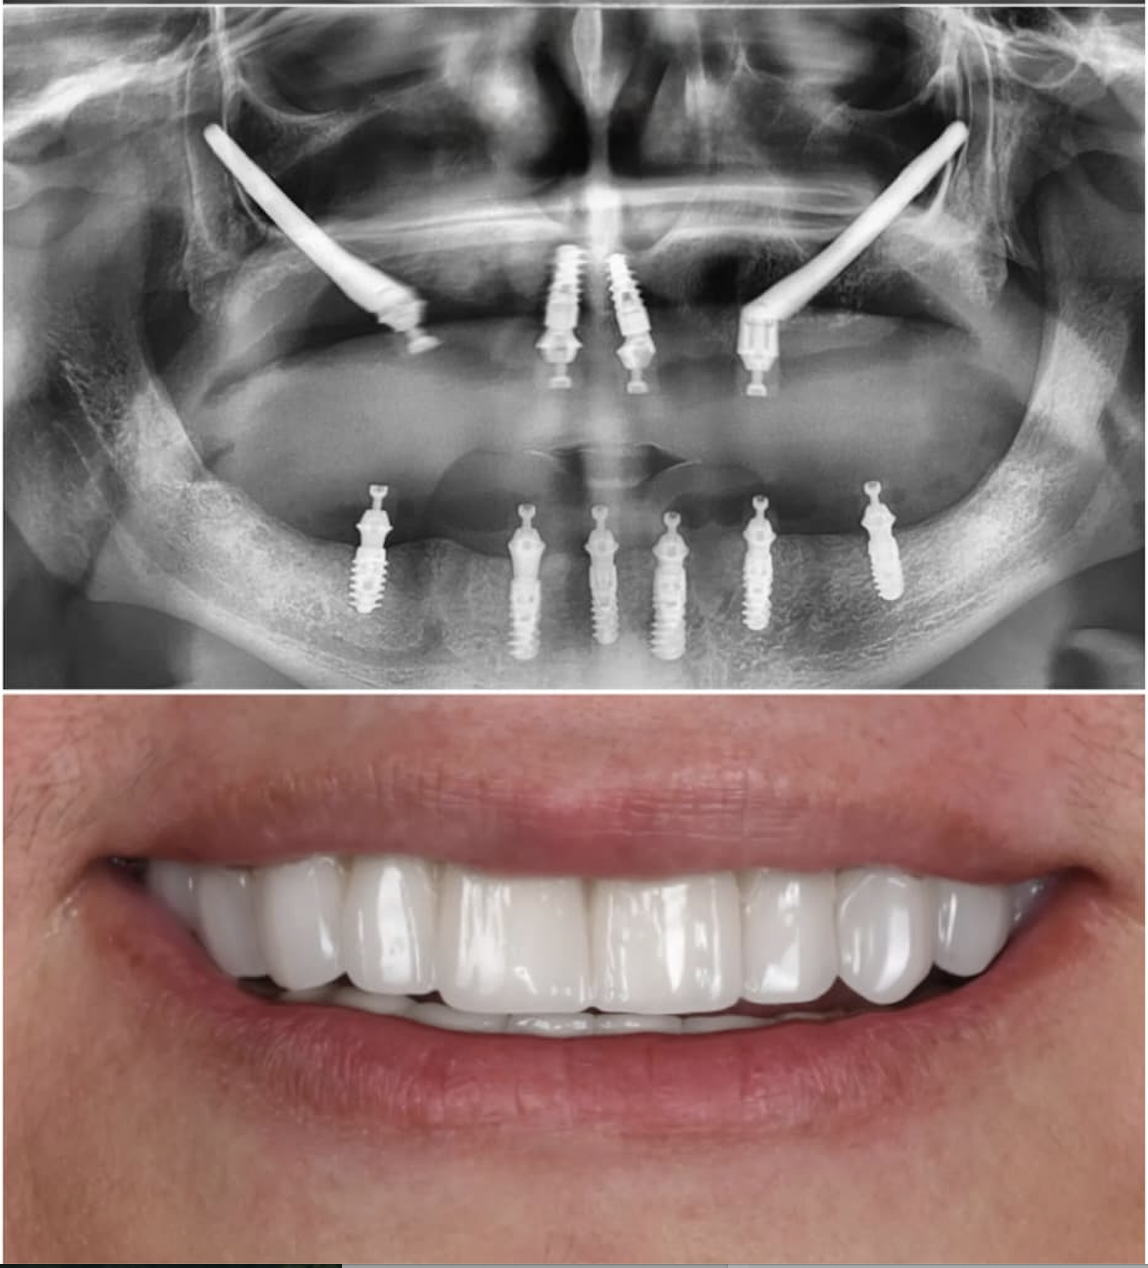

Our patient from Minnesota, USA, reached our clinic with severe bone loss issues. Thanks to the ZAGA Concept, they regained new and fixed teeth in just 24 hours using zygomatic implants.

Zygomatic Implants Case Study

Case Study

Advanced Zygomatic

Implant Rehabilitation

Fixed prosthetic rehabilitation with zygomatic implants for a patient presenting with extreme bone deficiency and failed previous implant attempts from another facility.

In this complex case where traditional implant treatments were technically impossible to apply, the ZAGA Concept allowed us to provide a stable, long-term solution through specialized zygomatic surgery, restoring both function and aesthetics.

• Removal of failed implants from external centers

• Severe bone loss management via Zygomatic Concept

• Full functional and aesthetic fixed restoration